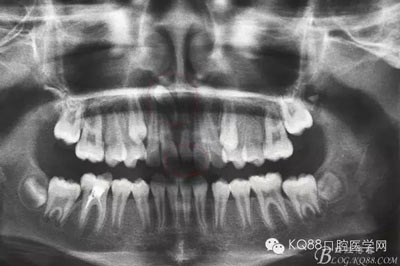

患者、賈xx、女、15歲。主訴:上前牙中間有一小牙,要求治療。口腔??茩z查:11和21正常萌出,在11和21之間有一多生牙,牙冠形態(tài)尚可,全景片檢查:11和 21之間有一多生牙,并且在該多生牙上方還有一倒置多生牙,牙冠與鼻腔緊鄰,無骨質(zhì)相隔。牙冠位于11牙根上方,牙根位于11和萌出多生牙之間。經(jīng)正畸科會診,建議拔除兩個多生牙,再確定正畸治療方案。診斷:多生牙 治療計劃:1.拔除兩枚多生牙 2.擇期行正畸治療,使11和21到正常位置?;颊咄庵委煼桨福炛橥鈺?/span>

圖1.術前患者的口內(nèi)照片,11和 21之間有一多生牙,牙冠形態(tài)尚可。

圖2.術前全景片檢查:除了已經(jīng)萌出的一枚多生牙外,在11根尖上方有一倒置多生牙,牙冠與鼻腔相通,牙根位于11和萌出的多生牙之間。